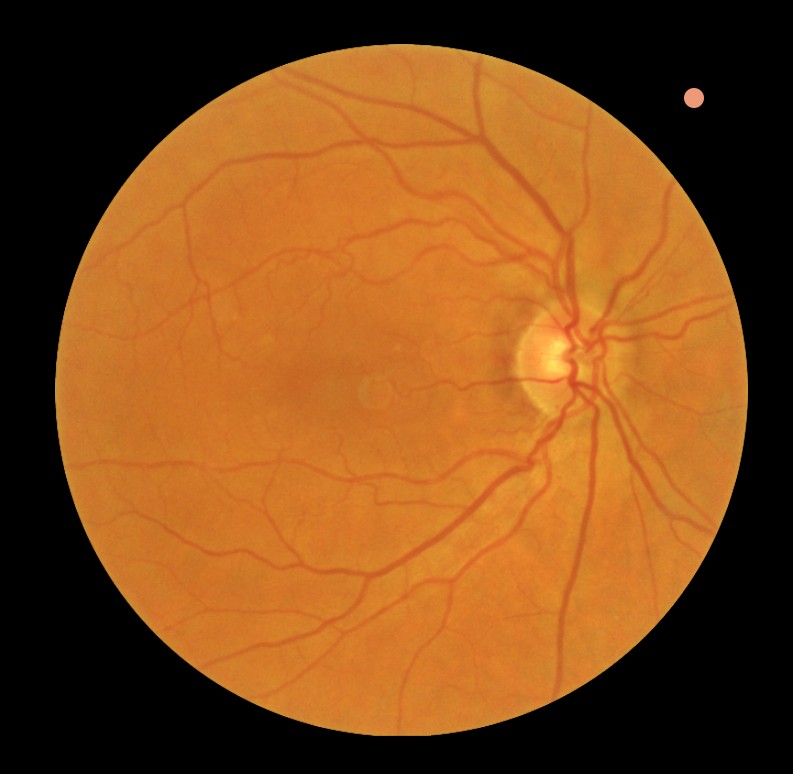

- Controle bij maculadegeneratie of diabetische retinopathie

Diabetes kan een belangrijke reden zijn voor een vervolgonderzoek, aangezien deze aandoening directe invloed kan hebben op de ooggezondheid. Regelmatige controles zijn essentieel om schade aan het netvlies vroegtijdig te signaleren en verdere achteruitgang te voorkomen.

Afhankelijk van de indicatie kunnen aanvullende onderzoeken worden uitgevoerd, zoals een gezichtsveldmeting, OCT-scan van de oogzenuw, of uitgebreide beoordeling van het netvlies met pupilverwijdende druppels.